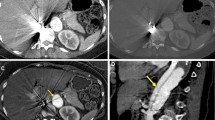

Two typical examples of TNC, dark-blood, and conventional CTA images are provided in Fig. 1, in a control subject and a patient suffering from Stanford A-type IMH. In both cases, dark-blood images provide improved visualization of the aortic vessel wall structure.